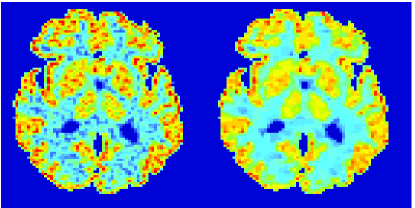

In the images shown in the figures we illustrate the calculated uptake rates of the FDG. Images for the CMRGlc can be obtained by directly scaling . In figure 1 we compare the result of using Patlak and TV-Patlak for estimating the uptake rates with respect to no noise, noise in the input function, Poisson noise in the sinogram, and finally with respect to the case in which the irreversibility assumption is violated but without noise in the sinogram or input data. In each case the histogram of the relative errors is given on the left, the Patlak image in the middle and the TV-Patlak on the right. The different scales in the histograms are due to the total number of results illustrated. When there is no noise (triples and ) the histogram illustrates results over all voxels but only one simulation, while for the noisy simulations the results are for all voxels over all realizations of the noise. The TV-Patlak images are more homogeneous in all cases and the relative errors are smaller. The figures clearly show the improvements of employing the TV-Patlak method as compared to using Patlak independently for each voxel. This is confirmed in figure 2 in which images with noise in the sinogram, positive and different noise levels in the input function are shown.

In figures 3 and 4 we illustrate the uptake rates and relative error in the uptake rates, respectively, calculated by Patlak, TV-Patlak, Patlak-GF and Patlak-MF for one simulated data case , i.e. , noise in the input function and Poisson noise in the sinograms. The uptake rate image generated by Patlak-MF is visually smoother than that by TV-Patlak, but the equivalent histograms show that the relative error is higher for Patlak-MF than for TV-Patlak; the Patlak-MF image is over-smoothed.